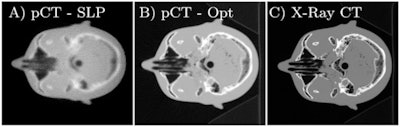

(A) Reconstructed proton CT of a head phantom from the original proton radiography; (B) the reconstruction with the optimized proton radiography; (C) the same slice of the x-ray CT phantom.Collins-Fekete and colleagues, who are based at Laval and other institutions in the U.S. and Belgium, developed their tool by exploiting the fact that protons are more likely to scatter through some tissues than others. Once a preliminary map of tissue has been delivered by proton imaging, therefore, it is possible to estimate statistically the likely route the protons must have taken in order to produce it. Then, it is possible to retrieve the image that would have been acquired, had the scattering not taken place. "The idea of using a path estimate to optimize proton radiography independently is a new one," Collins-Fekete said.

In computer simulations, Collins-Fekete and colleagues tested their statistical tool -- which they call a "maximum likelihood least squares estimator" -- on three different tissue phantoms. Adopting a widely used metric for the quantification of spatial resolution in imagery, known as MTF10%, the researchers found they could improve the resolution of a bare proton image with their tool by 65%. The resolution boost was the same as that delivered by existing methods, even though it required no prior radiographic imagery.